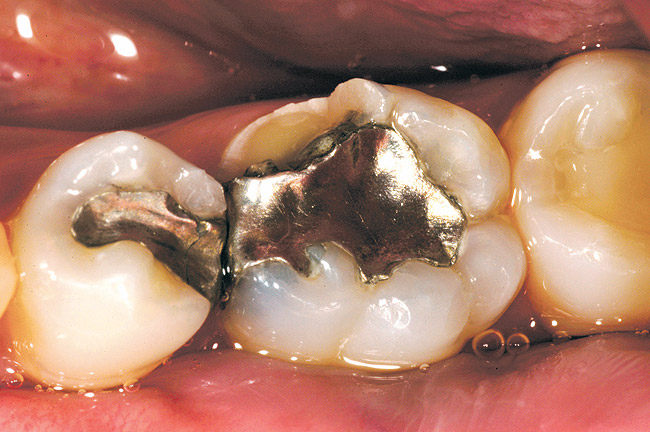

Figure 6a  A patient presents with a fractured mesiolingual cusp, a large amalgam restoration, and a crack line across the distal marginal ridge on tooth No. 19. Note only a thin rim of enamel remains at the site of fracture.

Figure 6a

While in vitro studies do not definitively demonstrate a correlation between fracture resistance and cuspal coverage, cuspal coverage is still considered important in instances where the remaining tooth structure is less than one third to one half of the intercuspal distance.22,23 Other factors that support cuspal coverage of posterior teeth are the position of the tooth within the arch, with molars subject to greater bite forces and, therefore, exhibiting a greater need for cuspal coverage.24,25 Cracked teeth also warrant cuspal coverage (Figure 1A through Figure 1C).26,27

All-porcelain restorations in posterior teeth require a minimum of 2 mm of occlusal clearance in the stress-bearing areas to provide adequate strength for the materials (Figure 2).28 While varying degrees of strength exist between feldspathic, leucite-reinforced, and lithium disilicate restorations, all have been shown to be successful with adequate occlusal thickness and proper management of occlusal forces.29 Higher strength porcelains, such as lithium disilicate, present opportunities for one-phase fabrication and may offer adequate strength at thicknesses less than 2 mm.30 More studies are needed to verify this hypothesis.